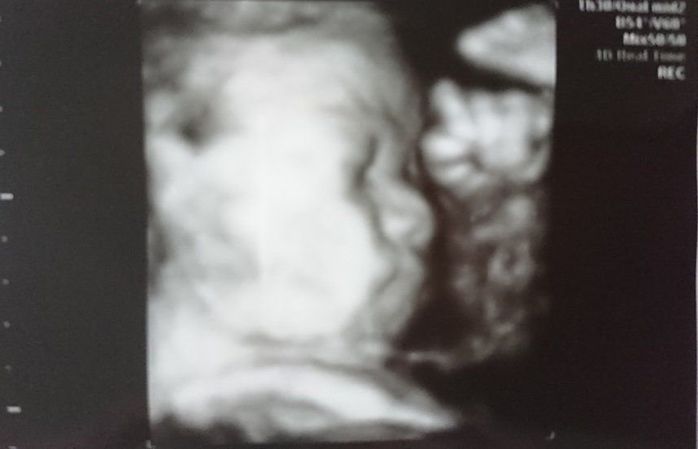

妊娠31週目のエコー写真

ふっくらと顔も体も丸みをおびてきました。3D画像は、横顔がはっきりと写っていて、手をギュっと握っているのが分かります。今の息子の寝顔にそっくりだと、改めて思いました。この頃の体の悩みは、腰痛と脚のむくみでした。家に帰り着圧ソックスを履くとかなり楽になりました。赤ちゃんの推定体重は1648gでした。